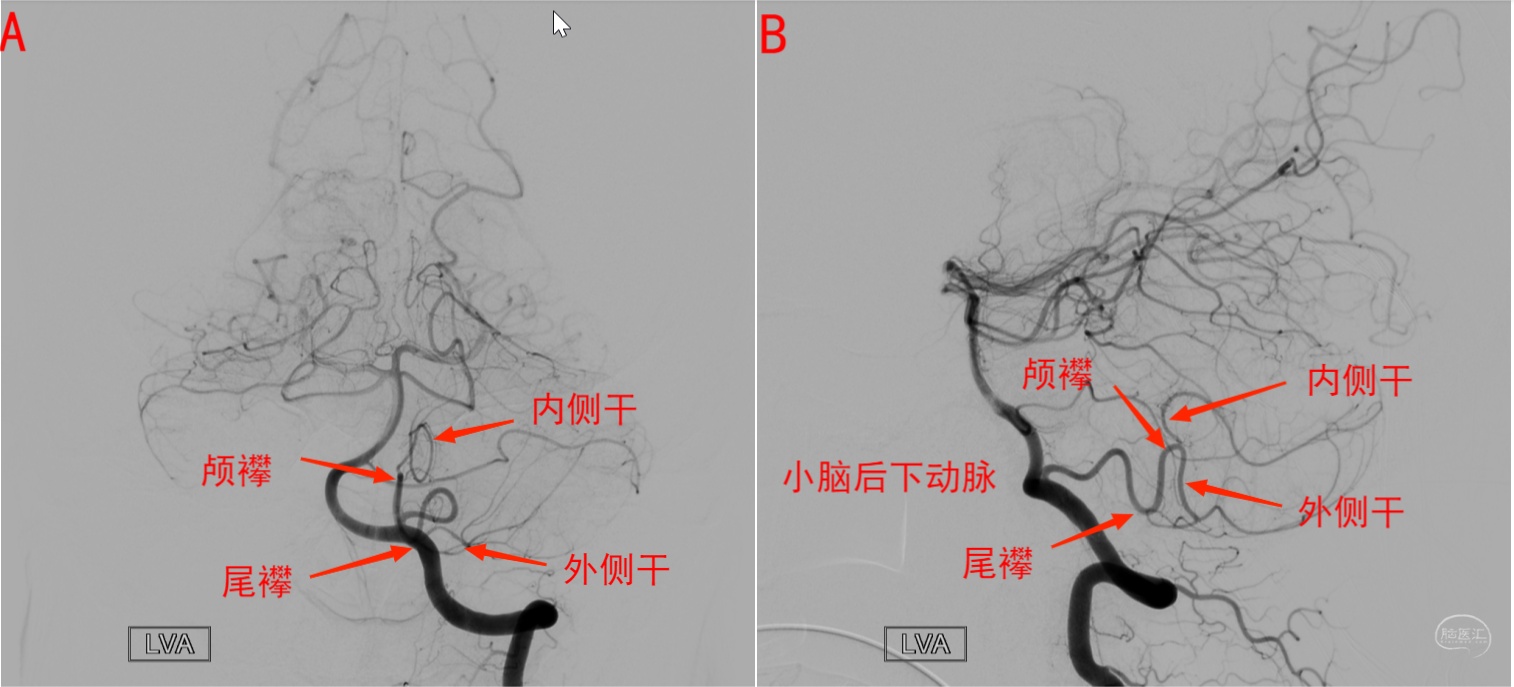

2.小脑后下动脉DSA影像解读

图9 正常小脑后下动脉DSA图像解读。图A为正位,图B为侧位,显示小脑后下动脉尾襻、颅襻、内侧干(蚓部供血)和外侧干(小脑半球枕下面供血)。延髓穿支一般发自于尾襻附近及其近端部位。